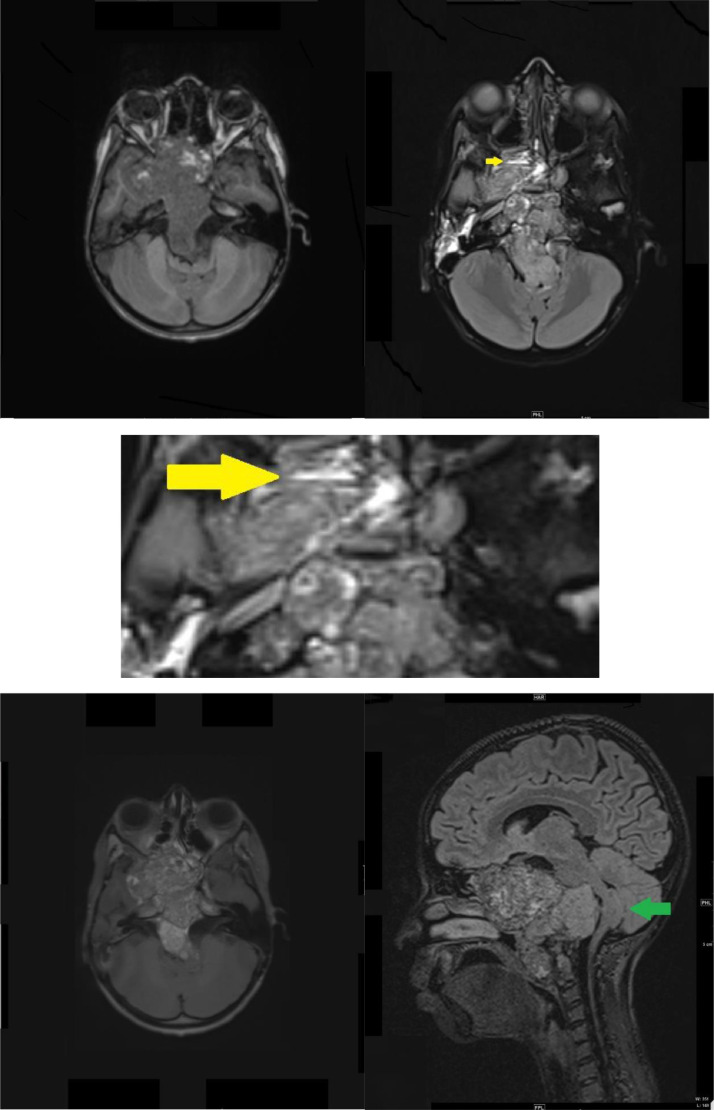

Brain magnetic resonance imaging (MRI) performed with intravenous (IV) gadolinium administration (Fig. 2) demonstrated a large destructive lesion at the base of the skull, centered within the clivus. It exhibited a heterogenous low signal intensity on T1-weighted imaging, with intervening linear hyperintense signal intensity. Additionally, few fluid levels were observed in the tumor in the right ethmoid sinus on fluid-attenuated inversion recovery (FLAIR) imaging, and multiple foci of diffusion restriction were seen. The lesion had intermediate heterogeneous signal intensity on T2/FLAIR images and heterogenous enhancement on post-contrast images. The intensity of the posterior component of the lesion was more enhanced than the internal component. There was disfiguring, deformity, and mass effect on the brainstem, with a U-shaped appearance. This simulated the thumb sign or thumbing of the pons. The peri-pontine cistern and the fourth ventricle were effaced. Inferiorly, the mass abutted the distal vertebral arteries bilaterally, with a destructive lesion at the C1 and C2 levels, causing encasement of the distal left vertebral artery.

Fig. 2.

Magnetic resonance imaging (MRI) of the brain axial T1 (A), axial FLARE (B), axial flare magnified (C), axial T1 post-contrast (D), sagittal axial fluid-attenuated inversion recovery (FLAIR) (E), demonstrated a large mass arising from clivus. (A) A heterogeneous low signal intensity with multiple foci of high signal intensity indicating intralesional hemorrhage was seen. (B, C) Intermediate signal intensities with fluid levels were noted (Yellow arrow) in the FLAIR images. (D) Heterogenous enhancement were observed in the post-contrast images. The posterior component of the lesion was enhanced compared to the internal component mass effect upon the brainstem with a U-shaped appearance. (E) Simulating the thumb sign or thumbing of the pons (Green arrow).